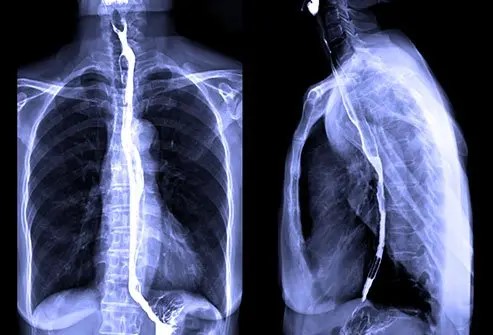

某晚Alfie正在刷TikTok,偶然看到一段视频,内容是一名女子在做钡餐造影检查,她吞下了一种白色粉状液体,让医生通过X光观察食物流向及是否存在阻塞。

(钡餐造影示意图,来自网络)

原来他的病症并不是压力所致,而是因为他患上了一种极其罕见的吞咽障碍 —— 食管贲门失弛缓症(oesophageal achalasia),每10万人中只有不到12人罹患。

这种疾病的具体表现为,食管肌肉无法正常收缩,导致食物无法顺利进入胃中,主要症状就是吞咽困难、胃酸倒流,还可能出现胸部感染、剧烈咳嗽以及食物反流等,间接导致体重下降、体内矿物质缺乏以及肌肉萎缩。